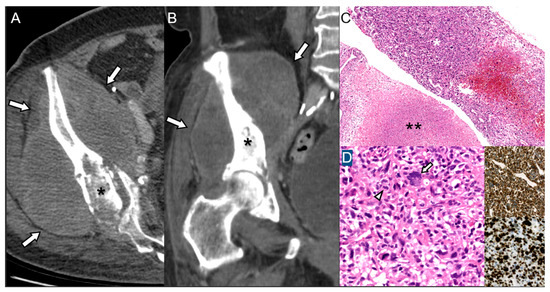

Malignant Transformation of Musculoskeletal Lesions with Imaging–Pathology Correlation—Part 1: Bone Lesions

by Hyang Sook Jeong, Seul Ki Lee, Jee-Young Kim, Changyoung Yoo and Min Wook Joo

Background/Objectives: Malignant transformation of bone lesions, although rare, poses a major diagnostic and clinical challenge. Common benign lesions (e.g., osteochondroma, enchondroma, fibrous dysplasia, giant cell tumor), non-tumorous conditions (e.g., chronic osteomyelitis, irradiated bone, infarction), and low-grade malignancies (e.g., low-grade osteosarcoma, chondrosarcoma) can evolve [...] Read more.

Background/Objectives: Malignant transformation of bone lesions, although rare, poses a major diagnostic and clinical challenge. Common benign lesions (e.g., osteochondroma, enchondroma, fibrous dysplasia, giant cell tumor), non-tumorous conditions (e.g., chronic osteomyelitis, irradiated bone, infarction), and low-grade malignancies (e.g., low-grade osteosarcoma, chondrosarcoma) can evolve into aggressive malignancies through distinct genetic, molecular, and microenvironmental pathways. Recognizing early malignant transformation on imaging is crucial for timely diagnosis and management. Methods: This review synthesizes current imaging characteristics, pathologic mechanisms, and clinical risk factors associated with malignant transformation of benign and low-grade malignancy bone lesions. Results: Atypical imaging findings and inaccurate biopsies can delay diagnosis. Aggressive features—such as cortical destruction, heterogeneous enhancement, and loss of internal matrix—should prompt further pathologic evaluation. Advanced imaging and a multidisciplinary approach with integrated clinicoradiologic–pathologic review are essential to minimize missed diagnoses. Patients with risk factors such as genetic syndromes, prior denosumab therapy, inadequate surgery, or prior radiation therapy require close monitoring or timely intervention. Conclusions: Radiologic–pathologic correlation remains central to distinguishing benign from malignant lesions. This review article emphasizes a comprehensive imaging-pathology overview of benign and low-grade malignancy bone lesions with malignant potential, aiming to improve diagnostic accuracy and outcomes in orthopedic oncology. Full article